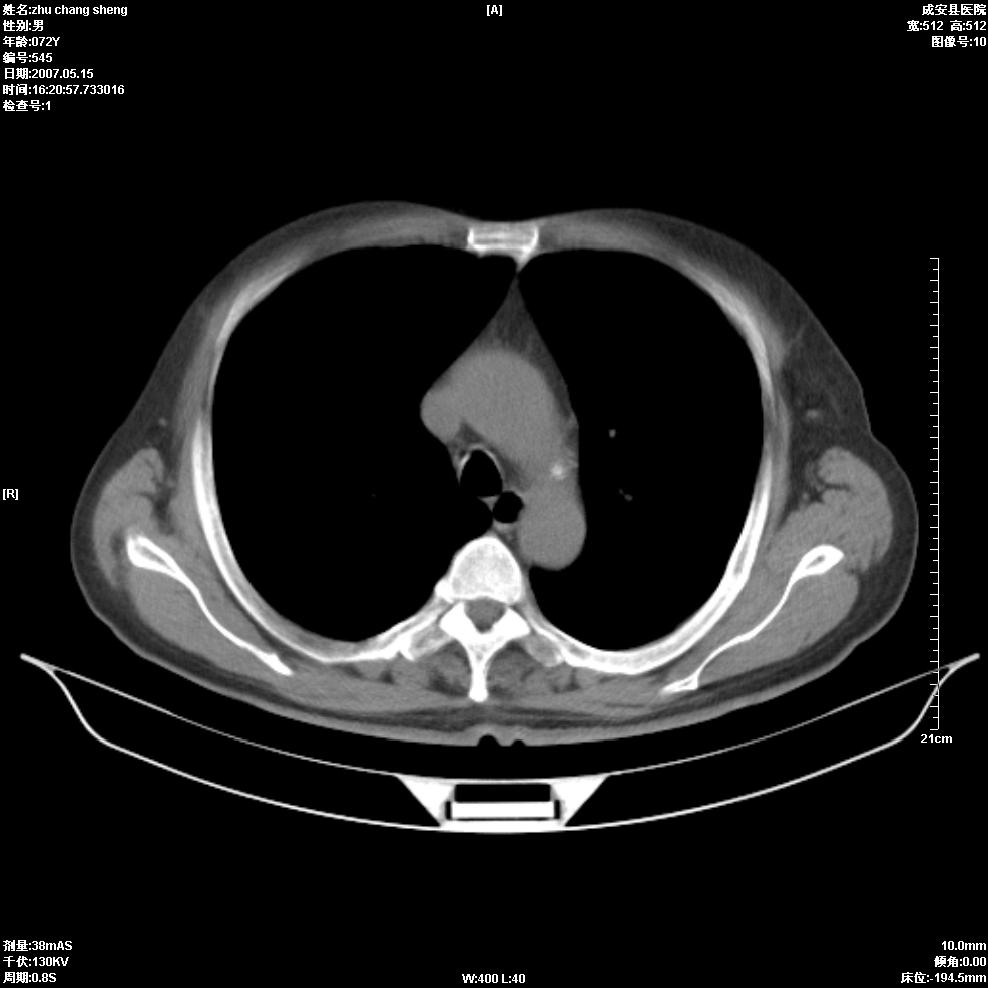

以下是引用医博云天在2007-5-15 19:10:00的发言:[br]心包积液,胸腔积液,心影增大,左心为主。

以下是引用zhangzhongshou在2007-5-15 20:21:00的发言:[br]心包积液可以肯定有,肿块显示不清,建议增强或mri检查。

以下是引用jinning在2007-5-15 21:06:00的发言:[br]心包积液可以肯定,建议增强或mri检查吧!

以下是引用拾荒者在2007-5-15 22:28:00的发言:[br]心包膜增厚,有少量积液,右室前壁示均匀软组织密度影,边界欠清,建议增强扫描或mri检查与室壁瘤鉴别。

以下是引用还珠格格在2007-5-19 9:50:00的发言:[br]病人与5月18日 做了核磁增强扫描 确诊为前上纵隔侵袭性胸腺瘤。